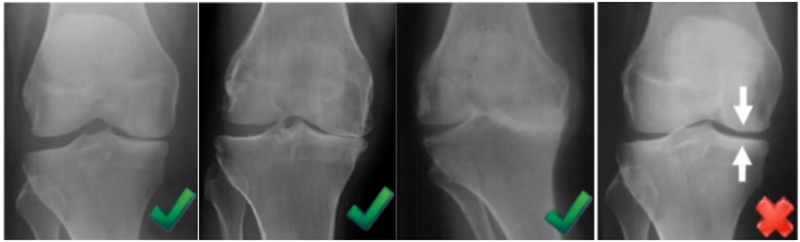

牛津单髁影像学判断的标准为通过负重正位片来判断内侧间室关节软骨的磨损程度。内侧间室关节间隙变窄,股骨内侧髁与内侧胫骨平台成“骨磨骨”状态,说明内侧间室软骨磨损丢失。如果没有在正位片观察到“骨磨骨”,则需要通过内翻应力位片或rosenberg位检查,找到骨磨骨的证据。如果以上均没有显示骨磨骨,需考虑关节镜检查,只有在达到“骨磨骨”的情况下才考虑行UKA。

外翻应力片可以辅助评价外侧间室关节软骨厚度是否正常,以及内侧副韧带功能是否完整。外侧全层软骨、外侧有骨赘的情况下都不是禁忌证,如外侧出现软骨磨损则为禁忌证。

外翻应力片还可以观察内侧间隙,如内侧副韧带出现挛缩,间隙狭窄,那么此时不适合单髁。

AMOA的X线正位的表现